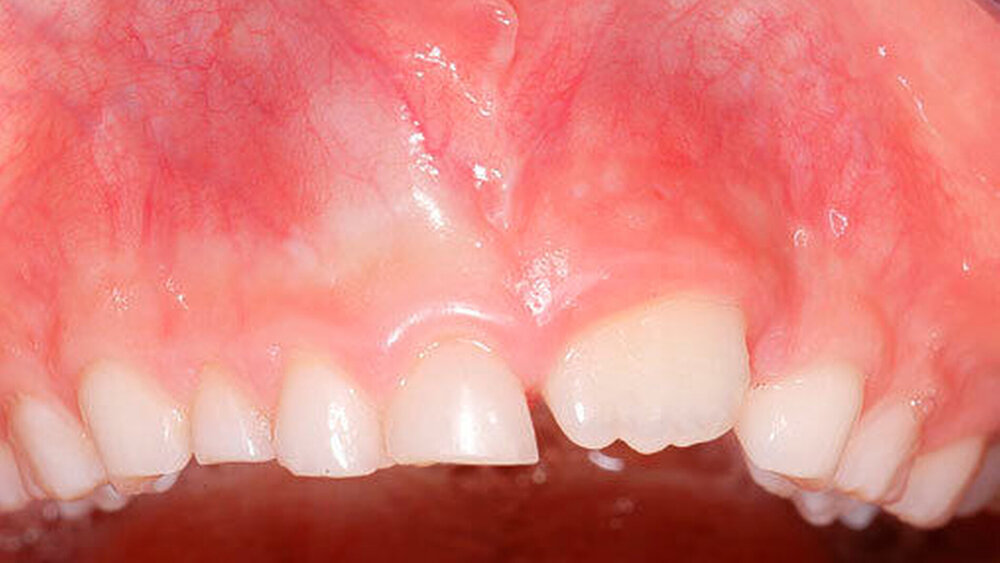

Die Prävalenz überzähliger Zähne wird im Bereich von 0,07 Prozent bis 0,6 Prozent für das Milchgebiss [Luten, 1967; Ravn, 1971; Järvinen Lehtinen, 1981; Magnússon 1984; Skrinjari Barac-Furtinovi, 1991; Yonezu et al., 1997; Chen et al., 2010] und von 0,3 Prozent bis 3,2 Prozent für die bleibenden Zähne [Luten, 1967; Bäckman Wahlin, 2001; Salcido-García et al., 2004; Leco Berrocal et al., 2007; Gündüz et al., 2008; Yagüe-García et al., 2009; Schmuckli et al., 2010; Fardi et al., 2011] angegeben. Die Mehrheit der überzähligen Zähne im Milchgebiss sind seitliche Schneidezähne im Oberkiefer, die meist mit einer normalen Morphologie und Lage durchbrechen (Abbildungen 1 bis 3) [Luten, 1967; Humerfeld et al., 1985; Garvey et al., 1999; Ferrés-Padró et al., 2009]. Der oft ungestörte Durchbruch und das Ausbleiben von Symptomen führen dazu, dass überzählige Zähne in der Milchdentition oft gar nicht diagnostiziert werden, und dies wird auch als Erklärung für die unterschiedlichen Prävalenzen überzähliger Zähne im Milch- und bleibendem Gebiss angeführt [Wang Fan, 2011]. Überzählige Zähne sind häufiger bei Männern als bei Frauen, wobei über ein Verhältnis von 1,18:1 bis 4,5:1 berichtet wird [Rajab Hamdan, 2002; Fernández Montenegro et al., 2006; Gündüz et al., 2008; Wang Fan, 2011]. In der Schweiz publizierten von Arx (1990) und Schmuckli und Mitarbeiter (2010) Geschlechterverhältnisse von 2,6:1, beziehungsweise 2,75:1. In einer aktuellen Arbeit von Mossaz und Mitarbeiter (2014) von Patienten aus dem Raum Bern lag dieses Verhältnis etwas ausgeglichener bei 1,61 zu 1.

Die überzähligen Zähne mit identischer Zahnform finden sich normalerweise beim oberen seitlichen Schneidezahn. Zusätzliche Prämolaren und Molaren können aber auch auftreten. Die Mehrheit der überzähligen Zähne im Milchgebiss sind vom identischen Zahnform-Typ und bleiben nur selten impaktiert oder retiniert.